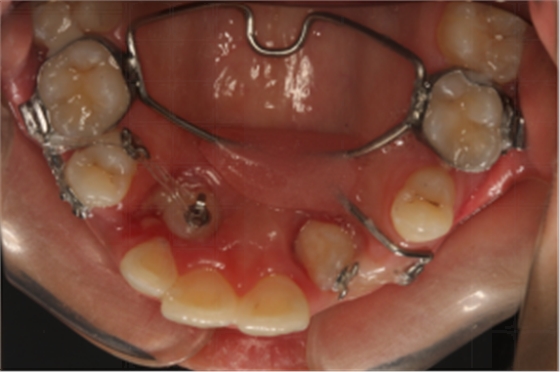

14:30-15:30 正畸患者的埋伏牙開窗術

【精彩病例】